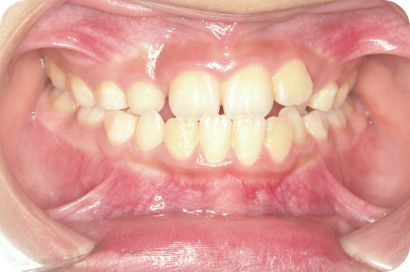

Nさん

Before

After

- 形態:咬合改善

- 機能:習癖の改善、咀嚼トレーニング、口腔周囲筋エクササイズ

- メリット:顎の正常な成長を促し、将来の抜歯や本格矯正のリスクを軽減します。正しい噛み合わせは全身の健やかな発育にも繋がります。

- リスクと副作用:お口周りの筋肉痛や疲労感が一時的に出ることがあります。また、毎日のトレーニングや癖の改善をご家庭で継続する必要があり、ご家族の協力が不可欠です。